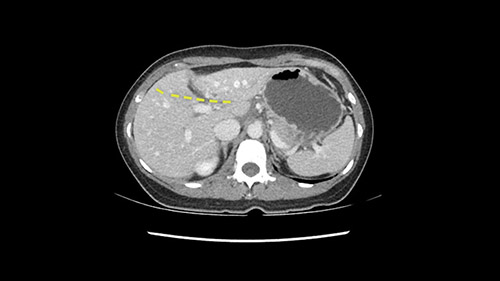

So if we look at the CT scan, on the axial, it’s a larger lesion. It’s about 6 or 7 or 8 centimeters. So it does look a bit threatening in terms of its resectability but if you really drill down deeply into the anatomy, and I think the coronal [imaging] is even better, you can see that the entire mass is on the patient’s left side of the falciform ligament. So it’s really only a left-sided tumor and not even really a left-sided tumor because Segment 4 is uninvolved anatomically.

None of the parenchyma is affected and this tumor is very exophytic; like many Hepatitis B hepatomas; and otherwise is resectable with either a wedge resection part of Segment 2-3 or a formal left lateral segmentectomy.

Some of my colleagues thought it may be involving Segment 4 and we’d need a formal left hepatic lobectomy, dividing anatomically: the left portal vein, left hepatic artery, left bile duct. But I didn’t think so, but you can see there is a challenge in terms of being certain where this tumor is located. So we’re prepared to do any of those 3 but my person view is that its going to be an exophytic tumor off of the left lateral segment and probably a wedge.